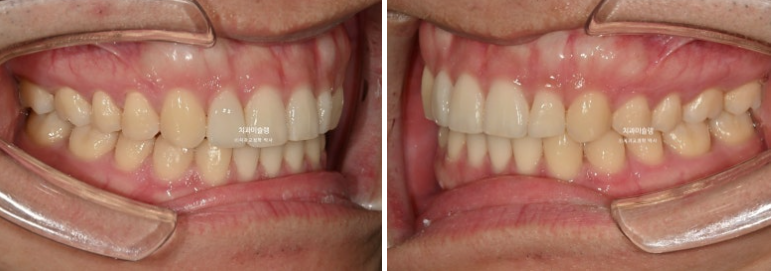

24.03~25.11

왜소치 덧니쪽으로 쏠려있던 앞니 중심선이 비로소 중간으로 맞춰졌습니다.

옥니의 개선으로 미소가 환해졌습니다.